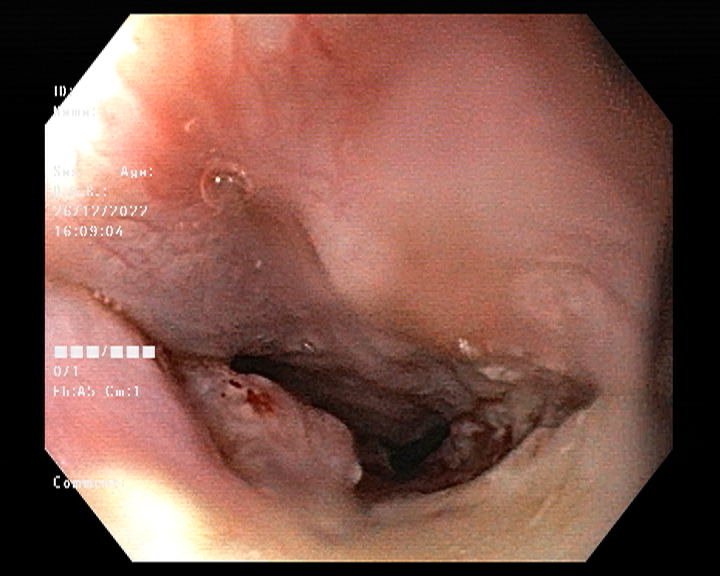

Endoscopy and colonoscopy are safe and accurate procedures used to directly examine the digestive tract and detect the root cause of chronic acidity, GERD, abdominal pain, bleeding, and bowel irregularities. These minimally invasive tests help identify ulcers, inflammation, infections, polyps, strictures, and early cancerous changes.

At Sapphire Gastroenterology Center, modern endoscopic equipment ensures precise diagnosis and, when required, therapeutic intervention during the same procedure. Based on findings, targeted treatment plans are created, including medication, diet guidance, and preventive strategies. Early diagnosis through endoscopy and colonoscopy plays a crucial role in preventing serious complications and improving long-term digestive health.